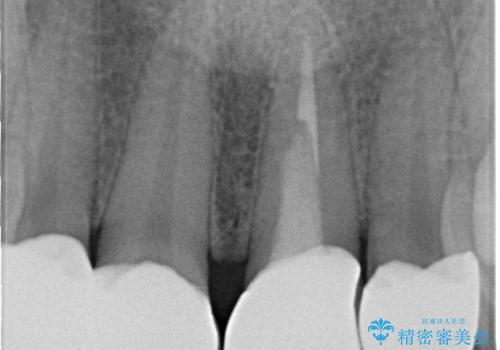

拡大鏡視野下で保険のプラスチック(コンポジットレジン)、虫歯、左上1の被せものを除去し、オールセラミッククラウンに適した形にしました。

歯と歯茎の間に圧排糸と言われる糸を入れてシリコーン印象材にて型どりをしました。